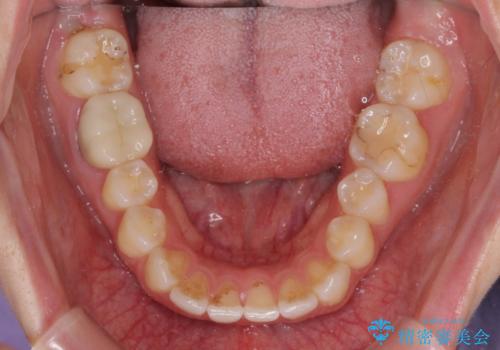

- 矯正治療の後戻りが気になるとのことで来院された患者様です。

上顎の後戻りをインビザライン・ライトで治療することとしました。

上顎のみの治療を希望されたため、咬み合わせをしっかりと改善することはできませんでしたが、審美面が大きく改善され、日常生活の機能面でも不具合を感じることはなく、大変満足していただきました。